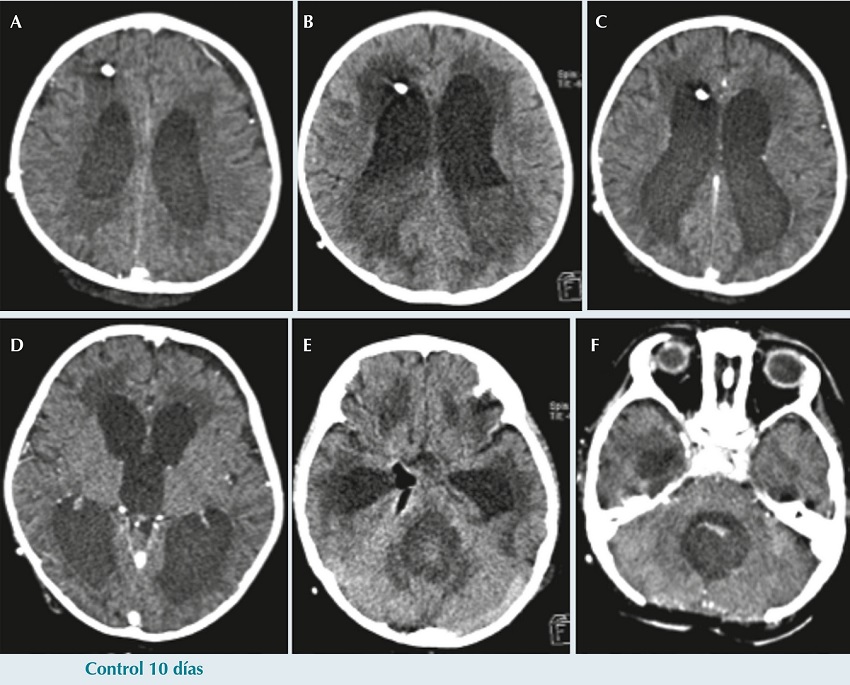

Al décimo día de la craniectomía presentó endotropía, somnolencia e hipertensión, realizándose tomografía axial computarizada cerebral donde se encontró hematoma hiperdenso residual en el lecho quirúrgico y se observó nuevo incremento en la talla ventricular, por lo que pasó a quirófano para exteriorización del sistema de derivación ventrículo peritoneal por hemorragia intraventricular (Figura 4). Se agregó fiebre hasta 38.6ºC de difícil control, por lo que se inició esquema antibiótico con ceftriaxona y vancomicina a dosis de sistema nervioso central, para cobertura de bacilos Gram negativos y cocos Gram positivos, respectivamente. En el cultivo de líquido cefalorraquídeo hubo desarrollo de Pseudomonas aeruginosa por lo que se suspendió ceftriaxona y se inició meropenem (120 mg/kg/d). Se reportó antibiograma de P. aeruginosa con resistencia a carbapenémicos, sensibilidad intermedia a piperacilina/tazobactam y sensibilidad a cefalosporinas de cuarta generación, por lo que se suspendió meropenem y se inició cefepima (150 mg/kg/d).

El paciente presentó deterioro clínico, somnolencia y dificultad respiratoria por lo que se pasó a ventilación mecánica y se realizó otra tomografía axial computarizada que mostró abundante líquido con detritus sugestivos de pus. Por este motivo, se decidió re-intervenir quirúrgicamente para retirar el sistema de derivación ventrículo peritoneal y colocar ventriculostomía externa (Figura 5). Posteriormente, continuó hemodinámicamente inestable, con datos clínicos de choque séptico sin respuesta a manejo intensivo persistiendo con taquicardia, hipertensión arterial y disminución en la saturación de oxígeno; finalmente, presentó paro cardiaco sin respuesta a maniobras de reanimación.